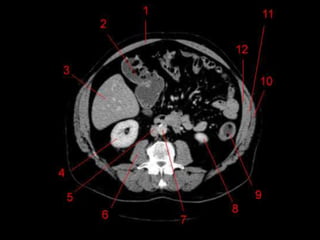

• TC: Tres fases

– Arterial (10 a 20 segundos)

– Fase venosa portal ( 30 segundos )

– Fase venosa hepática (60 segundos)

Técnicas de Imagem •US: Primeiro exame pedido ao: 1) dor no hipocondrio direito; 2) testes de função hepáticas anormais; 3) suspeita de malignidade. • TC: Tres fases – Arterial (10 a 20 segundos) – Fase venosa portal ( 30 segundos ) – Fase venosa hepática (60 segundos) • TC Portografia: Metastases.